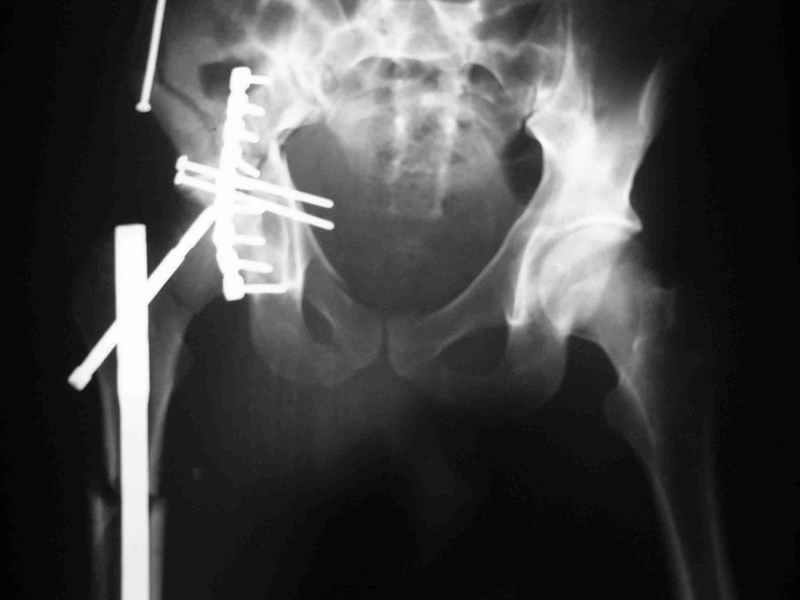

Не дождавшись советов, в понедельник прооперировал больного, заняло времени..., но все сделал в один этап: сначала фиксировал ипсилатеральный перелом бедра и шейки реконструктивным гвоздем Smith&Nephews, потом из расширенного илеофеморального доступа фиксировал перелом крыла подвздошной кости тягловым винтом, нейтрализующей пластиной заднюю колонну, и тягловыми винтами 3,5 мм переднюю колонну.

Несмотря на расширенный доступ, особой кровопотери не было, перелил только одну дозу эр.массы и на утро Нв- 10.5 и как ни странно больной не жалуется на сильные боли и стопа не *висит*, хотя при интраоперационной ревизии седалищного нерва обширная гематома в периневральной оболочке.

К сожалению, набора для ретроградного или антеградного реконструктивного штифтования в операционной нет, поэтому доставка заняла н-ное время. Вопрос, который возник у меня- по поводу оптимальной тактики хирургии: вся фиксация в один этап из расширенного доступа или последовательно сначала бедро и позже реконструкция впадины, комбинированный доступ к впадине отдельно к передней и задней колоннам или из расширенного илеофеморального одного доступа. Все-таки решил остановиться на одноэтапном подходе и спустя 5 дней (как раз и наборы привезли) из расширенного илеофеморального доступа сначала фиксировал реконструктивным штифтом Smith&Nephews бедро и

шейку (благо перелом шейки 2 типа -относительно стабильный) затем фрагмент крыла подвздошной кости Lag screw, далее пластина на заднюю колонну и винты в переднюю колонну.(с размерами и направлением винтов ошибка вышла:-((, но интраоперационно у меня была полная уверенность , что винты *ушли* в лонную кость).

Еще раз спасибо за комментарии и готовность помочь с имплантами. Постоп картинки в приложении,